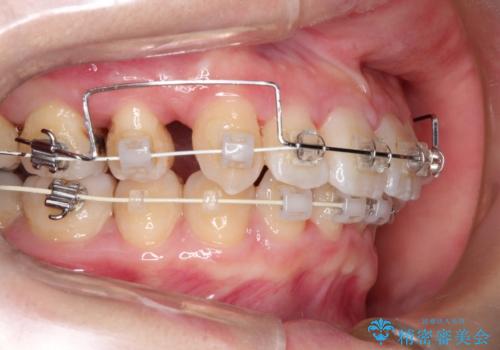

- 審美装置(ブラケット:白/ワイヤー:白)

初診時の歯並びの状態としては、上下ともに前歯部の中等度のがたつきがあり、下の前歯は本来生えるはずの歯が2本生まれつき欠損している状態でした。

また、上顎の歯は虫歯で歯冠が崩壊してしまって保存不可能な歯がありました。

抜歯ありワイヤー矯正にて治療を行い、抜歯する歯に関しては虫歯で抜歯が必要な部分を有効活用することで、健康な歯を保存するように努めました。

噛み合わせが深い過蓋咬合という状態でもあったため、下の歯の装置をつけたり、嚙み合わせを上げる(下の歯が見える状態にする)ことにたいへんに苦労した症例でした。